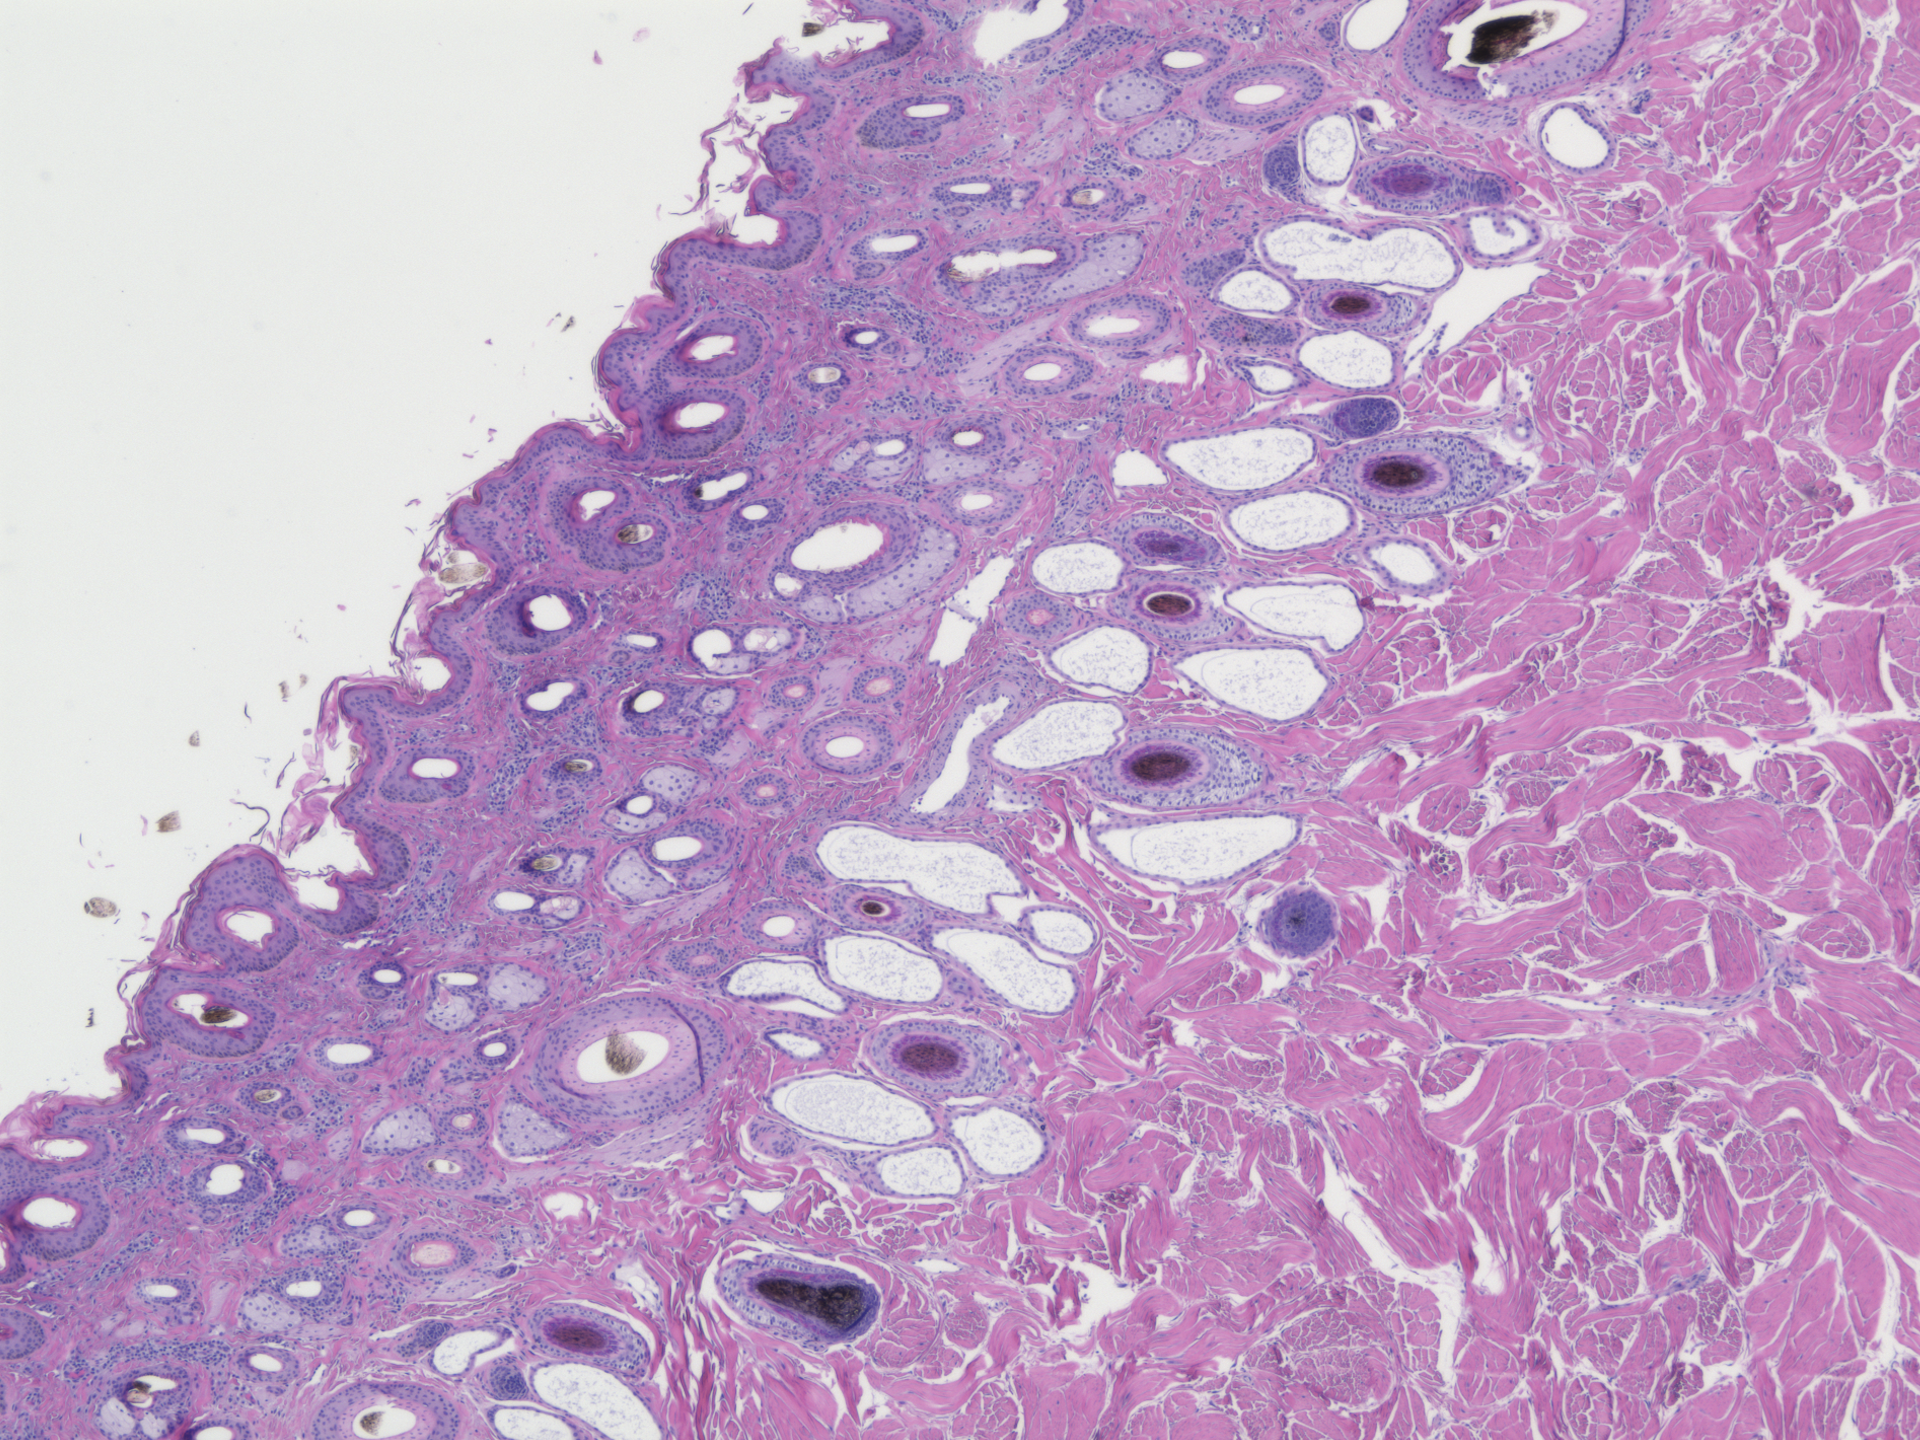

Heat stress alters DNA methylation patterns that can persist into adulthood.